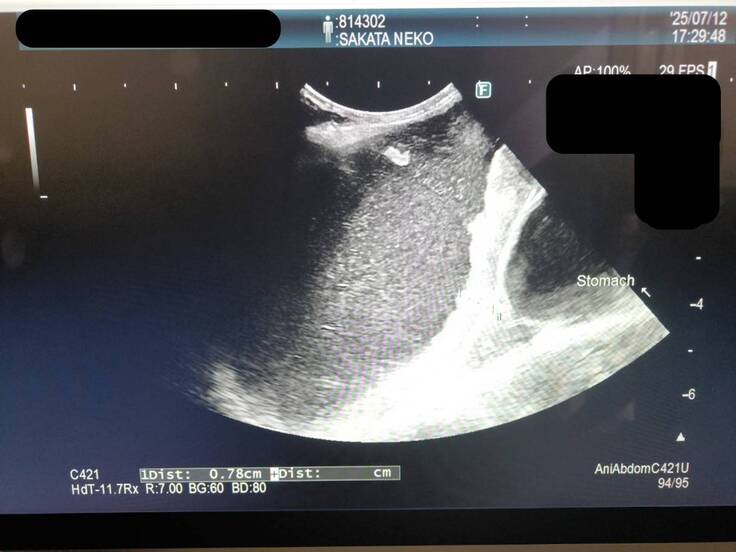

エコーでは、

小腸の腫瘍は抗がん剤前と比べると半分程の大きさまで小さくなっています。

ただ胃に問題が見つかり、胃液?がパンパンに溜まっていました。

↓胃のエコー

昨日の触診時点では溜まっていなかったと思います、とおっしゃっていたので昨日から今日にかけて溜まったようです。